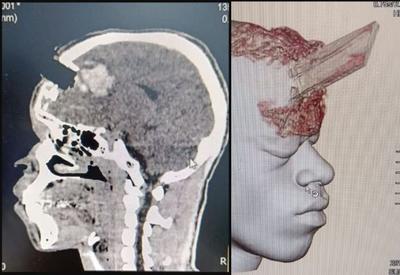

Brasil - 11/07/2024Estaca de madeira perfura cabeça de homem; cirurgia de retirada é considerada um sucesso